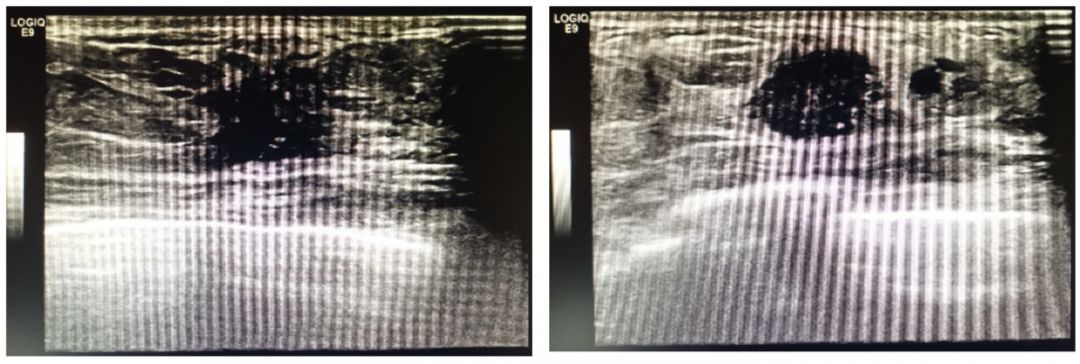

乳腺MRI: 双侧乳房对称,乳头未见异常。双侧乳房呈混合型,皮肤未见增厚。左乳外上象限及左乳内上象限分别可见一个直径约1.4 cm和1.0 cm大小的DWI高信号灶。增强扫描,左乳乳腺腺体背景中度强化,结构紊乱,左乳外上象限及内上象限可见不均匀强化,边缘模糊不清。右乳未见异常病灶,双侧腋窝淋巴结未见明显肿大。MRI诊断:左乳肿物,BIRADS 4a类。

图3 乳腺MRI检查